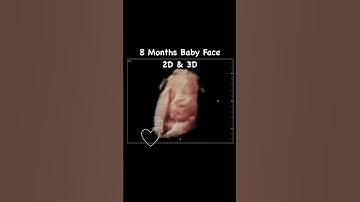

See your Baby face 😍 in pregnancy | 2D/ 3D/ 4D & HD baby Scan βœ… Pregnancy scan reports #shortsvideo